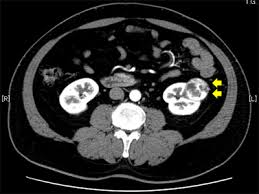

② 복부 CT(컴퓨터 단층촬영)

신장 종양의 위치, 크기, 혈관 침범 여부 등을 정확히 평가할 수 있어 진단과 치료 계획에 필수적입니다.